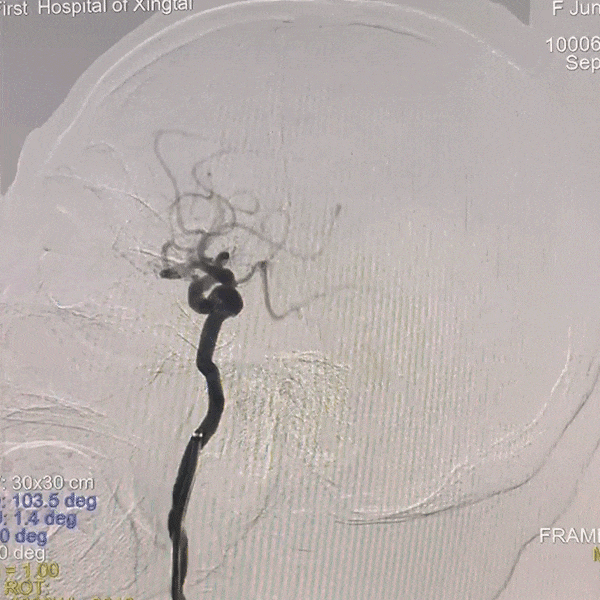

术后即刻影像

动脉长鞘怎么置入一技之“长”丨经桡及经股困难入路应用赛诺神畅APEX TRA GC™导引导管建立通路病例合集_https://www.jmylbn.com_新闻资讯_第16张

术后颅内正位造影

动脉长鞘怎么置入一技之“长”丨经桡及经股困难入路应用赛诺神畅APEX TRA GC™导引导管建立通路病例合集_https://www.jmylbn.com_新闻资讯_第17张

术后颅内侧位造影

患者术后即刻肢体肌力完全恢复。